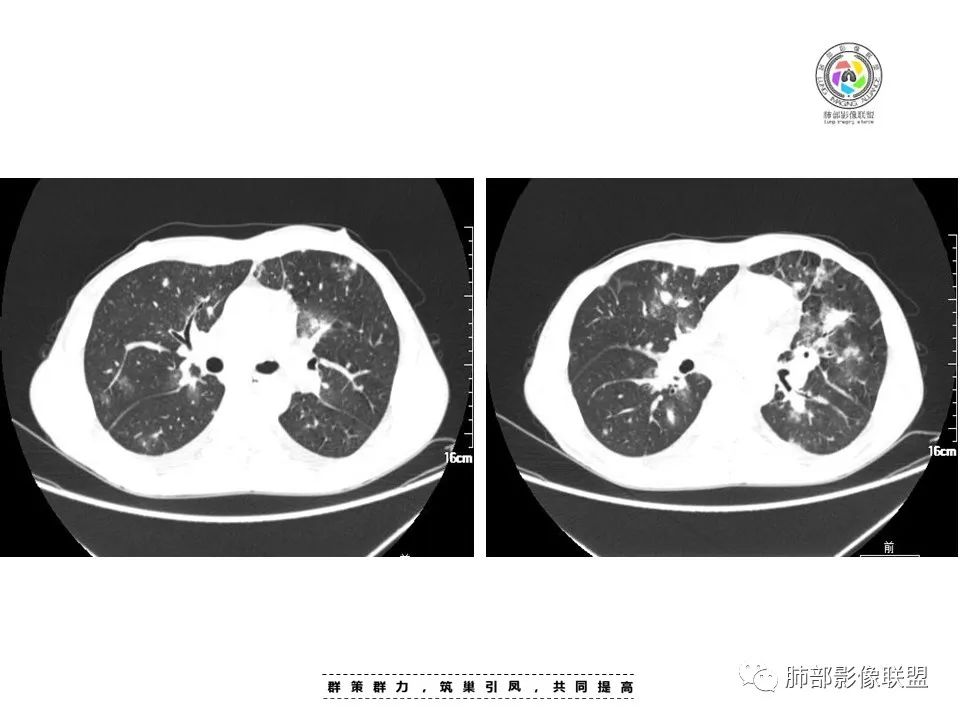

周一晚读病例:男性45岁,发热、纳差,全身散在暗紫色皮疹,结合CD4,符合HIV;肺部影像表现:两肺散在实性结节及磨玻璃密度影,实性结节伴晕征,部分沿支气管血管束分布,支气管血管束增粗,以两肺下叶为著,类似火焰征,双侧胸腔少量积液;首先考虑卡波西肉瘤,鉴别淋巴瘤增值性病变,淋巴瘤样肉芽肿/淋巴瘤,最后挂上马尔尼菲青霉菌病。

两肺弥漫性性结节状、小片状及片状带晕的病灶,煎蛋征、点晕征,主要分布两肺中下叶,病灶周围小叶间隔增厚呈网格状影,部分病灶累及胸膜,伴两侧胸膜增厚。

2.本例双肺小叶间隔增厚明显,多发结节影及片状实性密度影,沿血管支气管束分布为主,两侧较为对称,病灶多环以磨玻璃晕,边界不清。

双侧胸腔少量积液。双肺门及纵隔未见明确肿大淋巴结,纵隔结构间隙模糊。

1.结节型:两肺沿支气管血管束分布的结节影,呈火焰状或星芒状、挂果征,局部周围出血磨玻璃影(肺泡出血或水肿)。

2.支气管血管束增粗型:

肺门周围支气管壁呈“套袖样”改变。

斑片渗出影,部分融合呈“火焰样”,同时有火焰样结节,小叶间隔增厚等表现。